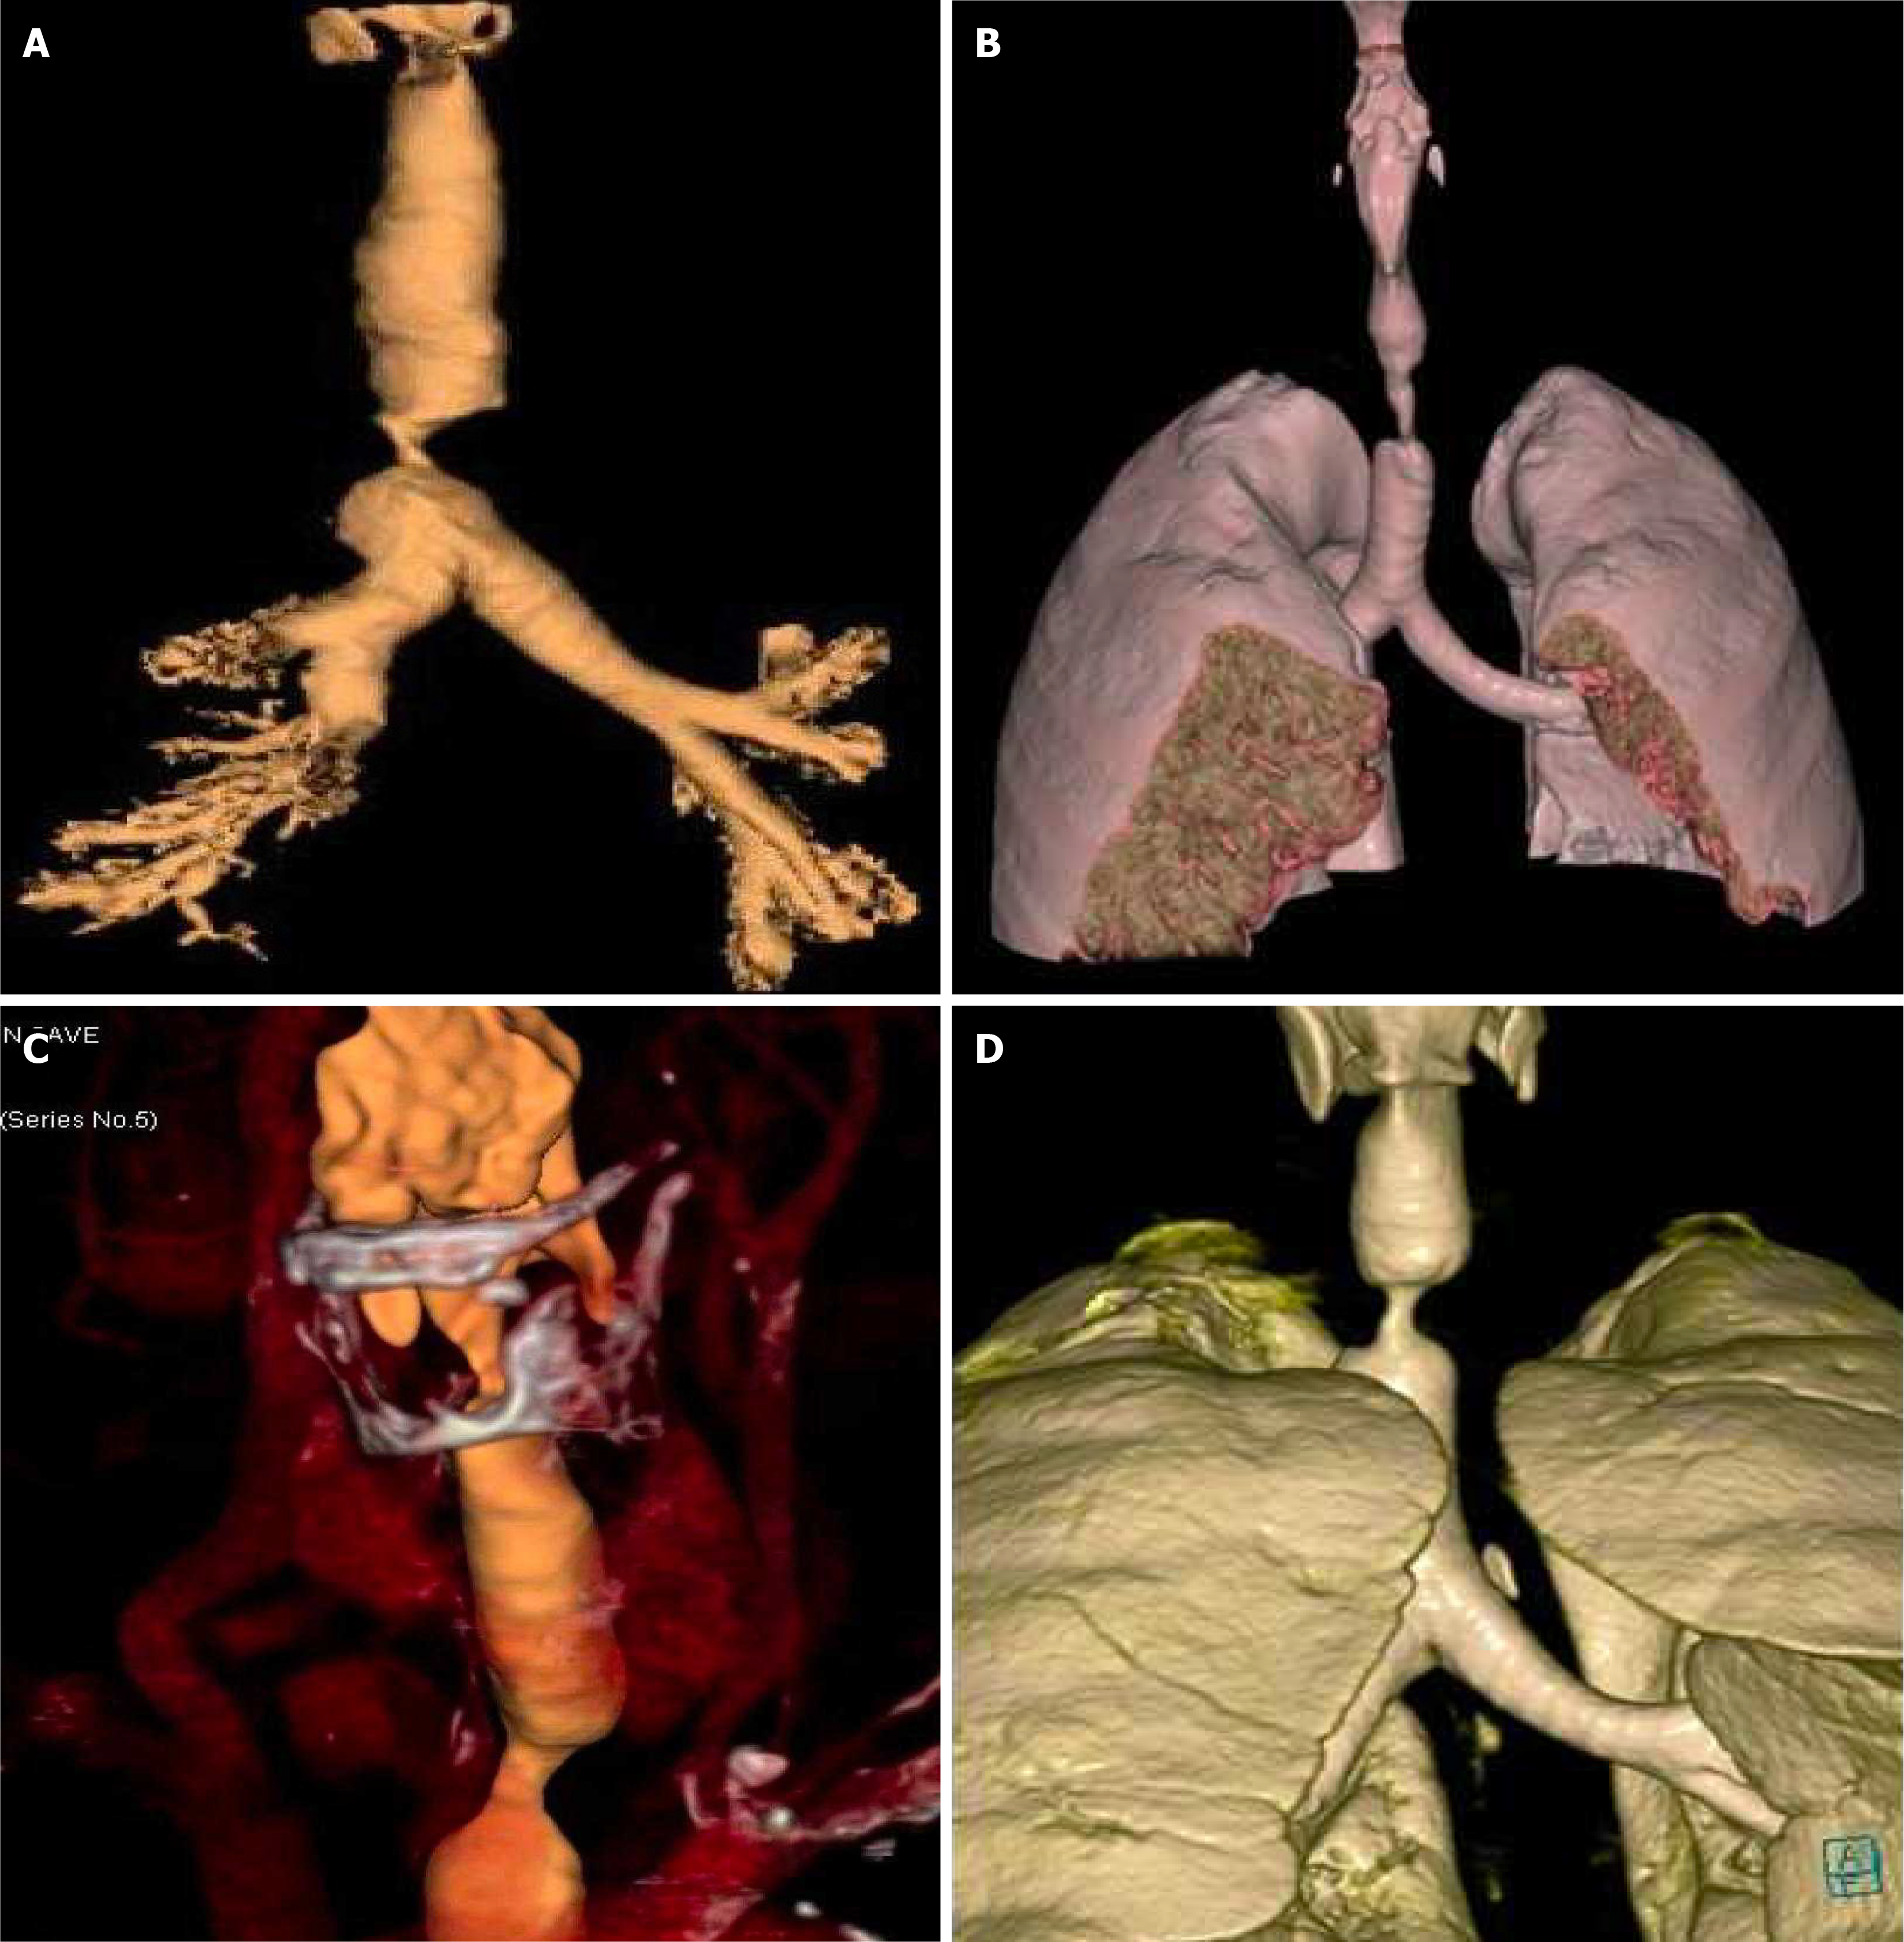

No systemic anticoagulation was administered in the perioperative period, and we did not observe any issues with circuit clotting or ECMO membrane dysfunction. Only one patient developed tension pneumothorax whilst on ECMO, which was unrelated to ECMO. This complication was unrelated to ECMO itself. The cause was tracheal perforation during intubation due to the sharp end of a Tribute endotracheal tube stylet in a patient with severe tracheal stenosis. The situation was recognized promptly and managed appropriately. We did not observe ECMO-related complications. Table 1 summarizes the patients’ data, including demographics, diagnosis, computed tomography (CT) findings, surgical and ECMO procedures, and outcomes. Figures 2, 3, 4 and 5 are examples of airway difficulties in our cohort (Fluoroscopy X-ray, CT scan, and bronchoscopy imaging). Pain and nutritional management were integral parts of patient care. Pain control was achieved using multimodal analgesia, including opioids and sedatives tailored to each patient's needs. Nutritional support was initiated early, with a preference for enteral feeding; parenteral nutrition was used when enteral access was not feasible or contraindicated.